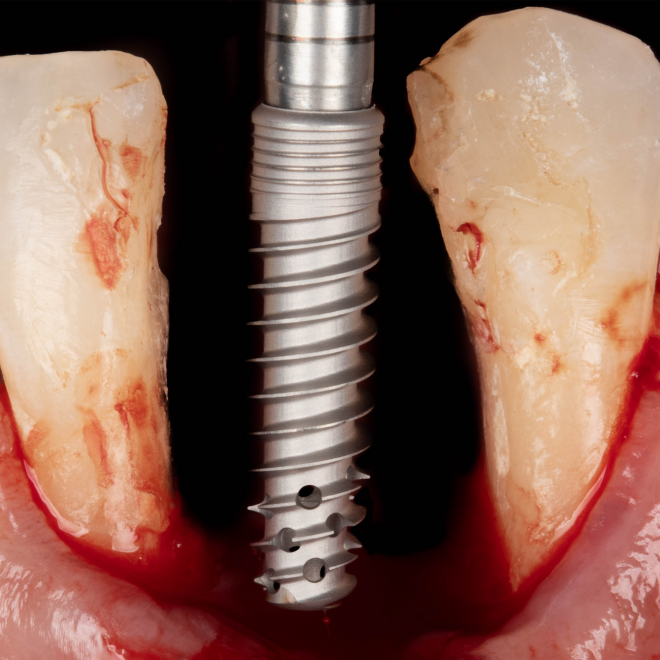

Desde 1985 tenho colaborado com o professor Per-Ingvar Brånemark e nos últimos anos, desenvolvi, juntamente com ele e Christian Brånemark, uma nova macro geometria do ápice do implante. Está parte apical do implante tem a função de reduzir o atrito, devido a seu corte preciso, controlando o torque de inserção, coletando lascas de tecido ósseo para o interior da câmara apical.

“Since 1985 I have been collaborating with professor Per-Ingvar Brånemark and during the last years, I have, together with him and Christian Brånemark, developed a new implant tip.This part of the implant is reducing friction, due to precise cutting, reducing insertion torque and collecting bone chips inside the tip part of”